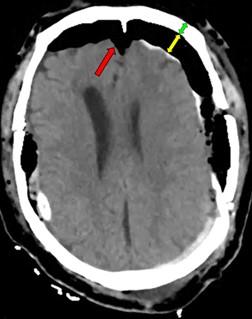

Intracerebral hemorrhage of basal ganglia, surgical management through transinsular transylvian approach. case report

GIUSEPPE ROJAS P.1a, JESÚS FLORES Q.2b